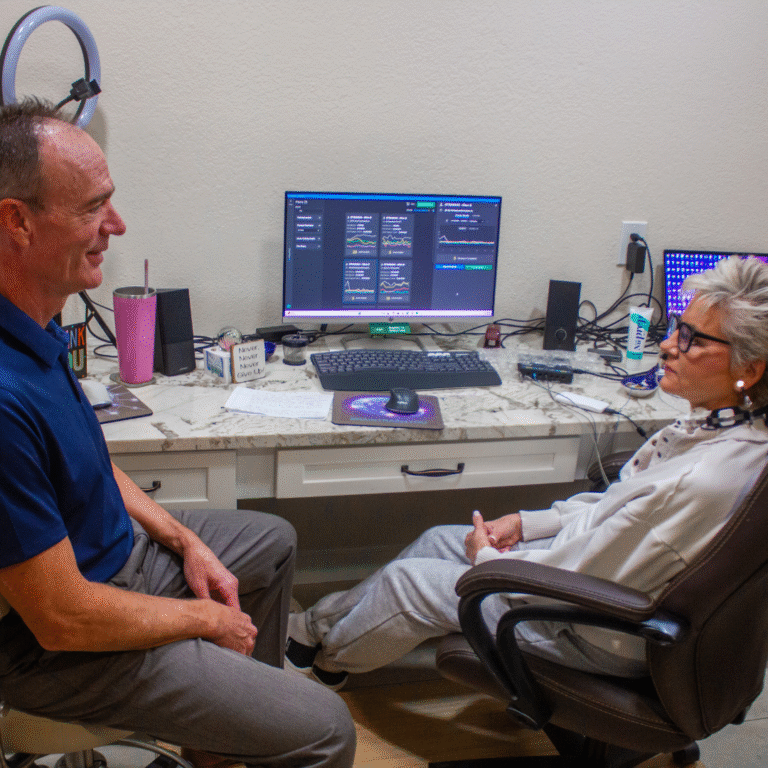

Living in a fast-paced world can often leave your nervous system in a state of “high alert.” For many residents in Scottsdale and the surrounding areas, chronic stress isn’t just a mental burden, it manifests physically as restlessness, insomnia, fatigue, and difficulty concentrating. At the Arizona Center for Neurofeedback, we believe that true wellness starts…